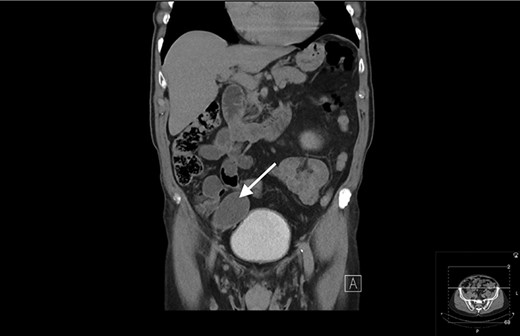

An 80-year-old gentleman was referred to General Surgery by the Urology department following an incidental finding on a computerized tomography (CT) urogram, performed for investigation of haematuria, which self-resolved. The finding was of a well-circumscribed hypodense mass in the right iliac fossa measuring 5.2 × 4 cm. There was subtle focus of calcification at its wall with no communication with the urinary bladder (Figs 1 and 2).

Coronal view of CT showing a well-circumscribed hypodense mass in the right iliac fossa.